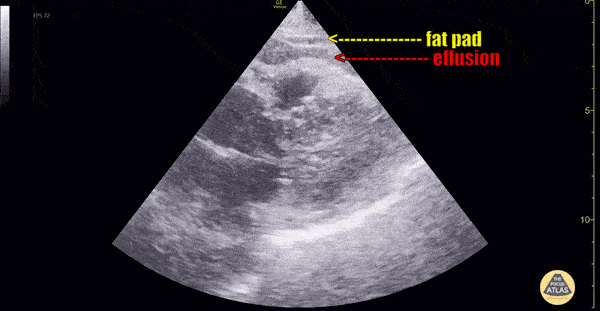

Echocardiography

The best Echocardiography POCUS clips.  This is free and open access medical education content. Right click to download.

Other Cardiac Pathology